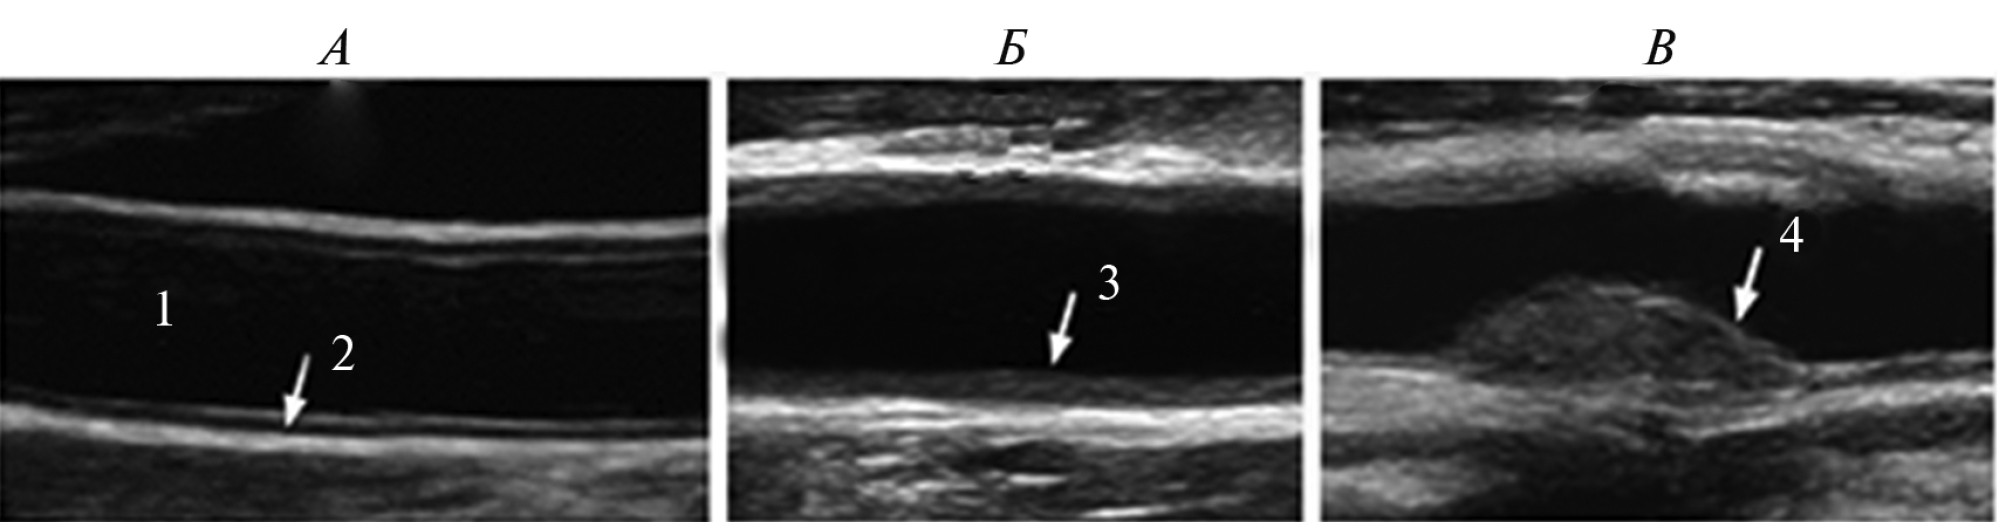

При первичном проведении дуплексного сканирования пациенты были распределены в зависимости от состояния стенки сонных артерий на три группы: “А-группа” – с сохраненной структурой стенки и определяемой анэхогенной медиа; “Б-группа” – с признаками утолщения комплекса медиа (нарушение трехслойной дифференциации слоев стенки); “В-группа” – определяется атеросклеротическая бляшка (АСБ) (рис. 3).

Рис. 3. Сонограммы состояние стенки при первичном сканировании (по группам). 1. Просвет сосуда. 2. Неизмененная стенка. 3. Утолщение комплекса интима-медиа. 4. Сформированная атеросклеротическая бляшка. А, Б, В — обозначение групп пациентов.